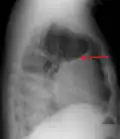

Pleural effusion Anteroposterior Chest X-ray of a pleural effusion. The A arrow shows fluid layering in the right pleural cavity. The B arrow shows the normal width of the lung in the cavity

When a pleural effusion has been determined to be exudative, additional evaluation is needed to determine its cause, and amylase, glucose, pH and cell counts should be measured.

The most common causes of exudative pleural effusions are bacterial pneumonia, cancer (with lung cancer, breast cancer, and lymphoma causing approximately 75% of all malignant pleural effusions), viral infection, and pulmonary embolism.